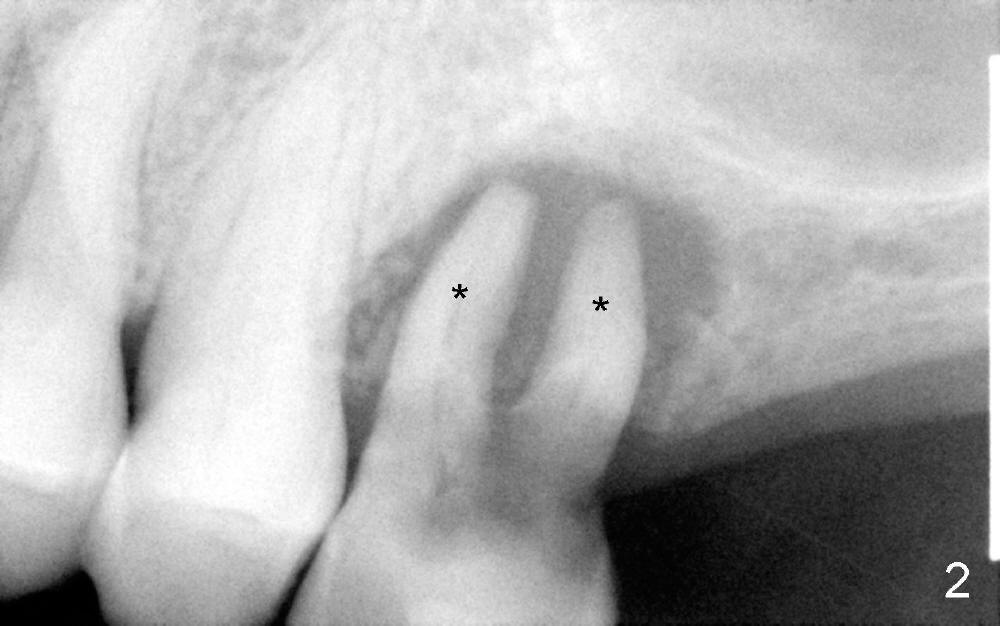

A 78-year-old lady has history of osteoporosis and history of taking Fosamax (Alendronate). Her upper left 1st molar needs extraction (Fig.1). The latter, appears to be easy, since the palatal root has lost. The remaining buccal roots have no bony support (Fig.2). Immediate implant should not produce extra trauma, leading to osteonecrosis.